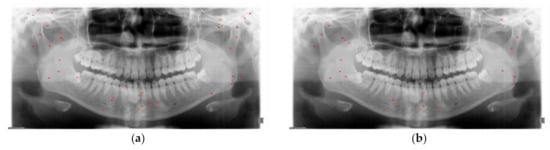

2.2.1. Data Augmentation

3.2. Detection Results